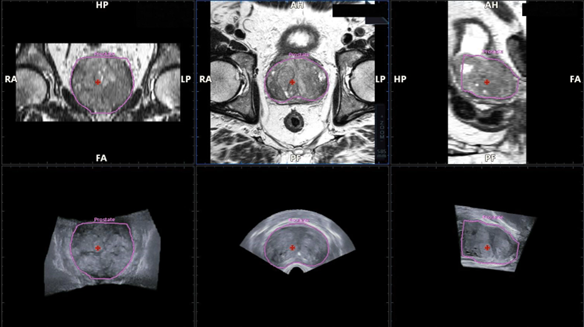

Una de las principales características de esta tecnología es la segmentación y sincronización automáticas de imágenes de RMN y US, realizadas mediante IA. Gracias a ello, el médico puede obtener una visión multimodal completa y en tiempo real, en una interfaz única e intuitiva. Esta integración no solo mejora la experiencia de uso, sino que también reduce la carga cognitiva del profesional, quien puede concentrarse plenamente en la atención al paciente.

El sistema incorpora además un seguimiento electromagnético de alta precisión, capaz de detectar en todo momento la localización exacta de la sonda. Con esta información, sincroniza las imágenes de resonancia con las de ultrasonido y permite identificar lesiones sospechosas en tiempo real. De esta manera, se mejora sustancialmente la exactitud en la toma de muestras, reduciendo el riesgo de errores y la necesidad de repetir procedimientos.

El software está diseñado para trazar automáticamente el volumen prostático y ofrece la posibilidad de definir hasta 25 blancos diferentes para la biopsia. Esta capacidad amplía las opciones de planificación del procedimiento, permitiendo al especialista explorar en detalle distintas áreas de interés dentro de la glándula prostática.